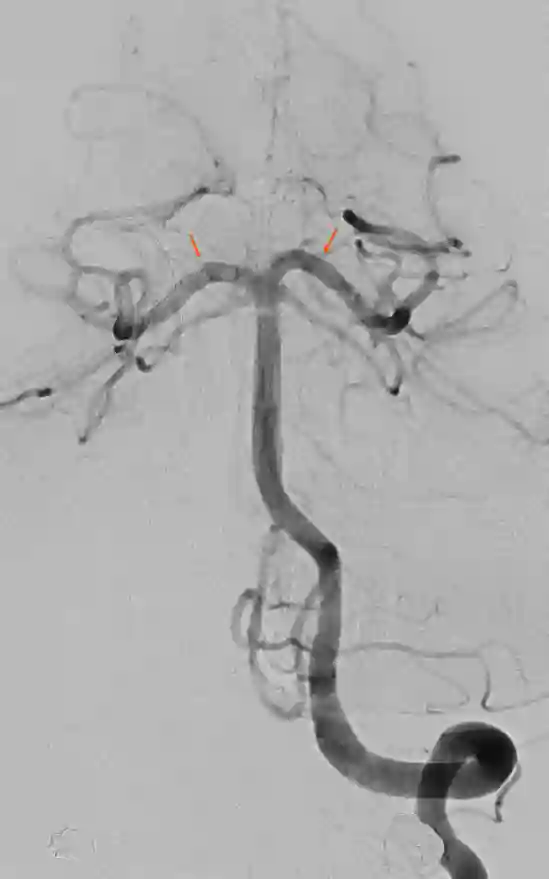

Arteria cerebri posterior DSA Angiographie

Digitale Subtraktionsangiographie des hinteren Stromgebiets mit Darstellung der Arteria cerebri posterior beidseits (roter Pfeil).